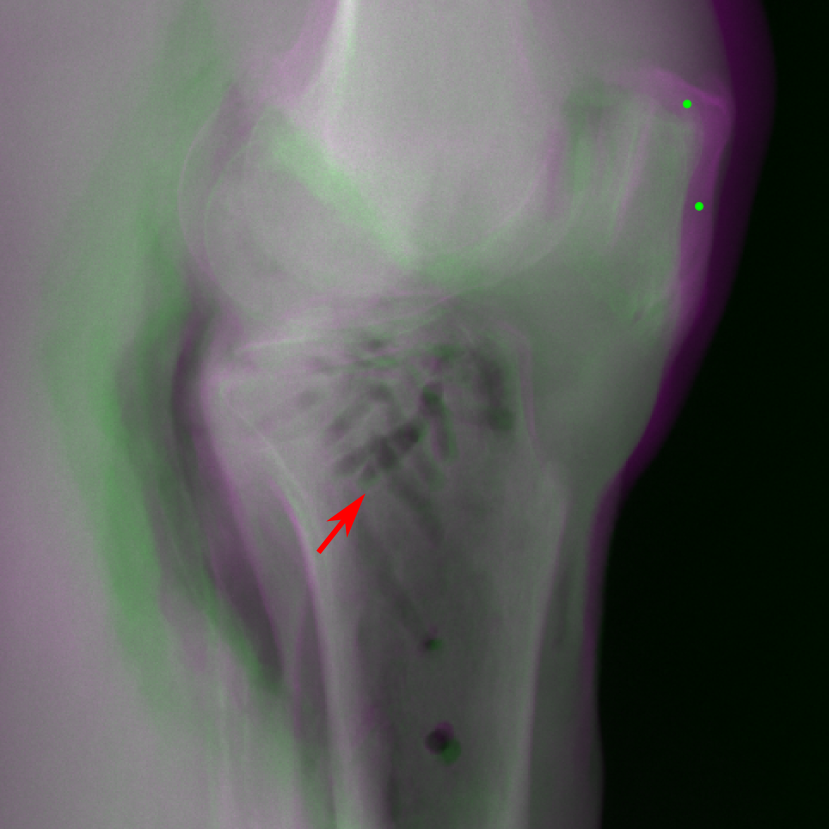

The complementary view setting for learning perspective deformation is also evaluated on real CBCT projection data. In this evaluation, real CBCT projection data from a dataset of knees with metal implants is used for testing, while DRRs created from volumetric CT datasets with inserted metals is used for training. Three exemplary DRR perspective projection images for training are displayed in Fig. 13, in which synthetic metal implants are inserted [34]. The appearance, e.g., image contrast and metal image resolution, of such DRR training images is different from that of real projection images in Fig. 14. In Fig. 14, the results for three knees, with and without metal implants, are displayed. The first and second rows are the 0superscript00^{\circ} and 180superscript180180^{\circ} perspective projections, respectively, rebinned to the virtual detector with geometric calibration based on their respective principal points and projections of the world origin. The third row displays their difference images, where the magnitude of deviation increases from the center towards the outside like it does in DRRs with an ideal scan trajectory (e.g., Fig. 6(e)), although real projection data suffer from various physical effects like beam hardening and Poisson noise. The fourth row displays the RGB stacks of 0superscript00^{\circ} and 180superscript180180^{\circ} perspective projection images. The magenta and green regions indicate structures with considerable perspective deformation, for example, the knee patella in Fig. 5.4, the top parts of the two metals in Fig. 5.4, and the bottom two screws in Fig. 5.4. The fifth row displays reference images, which are orthogonal projections of iterative reconstruction volumes from measured CBCT projection data. In the reference images, a total of five landmarks are selected, with the positions being marked by the green dots: In Fig. 5.4, two positions at the edges of the knee patella are marked; In Fig. 14(e) and Fig. 14(f), one position at the left edge of the fibula is marked for each image. In addition, a rectangular frame for the two metals is marked by the green dashed lines, while its width and height are indicated by the green solid lines, which are 29.71 mm and 111.99 mm, respectively. In Fig. 14(f), the centerlines of the bottom two screws are sketched by the green lines, which have the lengths of 17.14 mm (middle screw) and 19.38 mm (bottom screw). The corresponding rectangular frame for the two metals and the screw centerlines in the perspective projection images are marked as well, but in red color. In Fig. 14(a), the width and height of the metals are 32.56 mm and 109.85 mm, which have deviations of 2.84 mm and -1.95 mm to the reference ones, respectively. In Fig. 14(b), the centerline lengths are 18.91 mm and 19.54 mm, which have deviations of 1.77 mm and 0.16 mm, respectively. Although the bottom screw has little length deviation to the reference, the orientations of both screws are obviously deviated. The sixth row shows the results of Pix2pixGAN using 0superscript00^{\circ} and 180superscript180180^{\circ} polar inputs. For all of the landmarks, the green reference dots are all located accurately in the Pix2pixGAN images. The rectangular reference frame also accurately covers the metals in Fig. 14(g). In Fig. 14(h), although the two red centerlines do not exactly overlap with the green one, they are very close in lengths and orientations. Please zoom in for better visualization.

Figure 18: An example from the real cadaver data, where the Pix2pixGAN predicted metal rod is distorted (indicated by the red arrow) and certain K-wire shadows from perspective projection images remain (indicated by the blue arrows).

In the real cadaver data, certain metal implants are distorted in Pix2pixGAN predictions. For example, the long metal rod indicated by the red arrow is no longer straight in Fig. 18(c), although its position is between the corresponding magenta and green rods in Fig. 18(b). Another limitation is that certain structures like thin K-wires from 0superscript00^{\circ} and 180superscript180180^{\circ} perspective projection images will remain as shadows in the Pix2pixGAN prediction, for example, those indicated by the blue arrows in Fig. 18(c).

The RGB stack of two complementary views provides a practical way to identify which structures suffer from perspective deformation, as displayed in Fig. 6(f) and Figs. 14(j)-(l). Note that this is a sufficient but not necessary condition. The colorful structures, which deviate between two complementary views, must suffer from perspective deformation, given sufficient geometric calibration. However, certain structures which appear grey may also suffer from perspective deformation, due to the symmetry with respect to the virtual detector. For example, the grey cylinder background in the bead phantoms (Fig. 6(f)) also suffers from perspective deformation. Nevertheless, the networks are still able to correct these regions, as displayed in Fig. 9. This indicates that the networks exploit not only geometric features provided by the complementary view but also object/task-specific features for learning perspective deformation. Human anatomical structures are approximately symmetric with respect to the body’s mid-sagittal plane. However, the mid-sagittal plane typically does not overlap with the virtual detector plane in practice. Therefore, structures with perspective deformation are still indicated by colors (See Fig. 7 in supplementary material). Such geometric information can still be exploited by neural networks, as demonstrated by the superior performance of the complementary view setting on the chest and head data (Fig. 10 and Fig. 11).